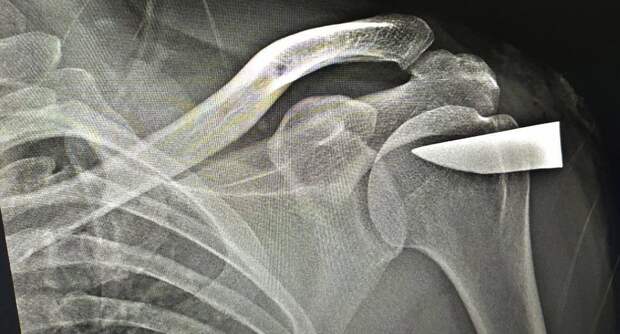

Обломок клинка длиной шесть сантиметров извлекли из плеча жителя Подмосковья. Пациент при этом признался, что не помнит, как получил такую серьезную травму. Помощь мужчине оказали специалисты Можайской больницы.